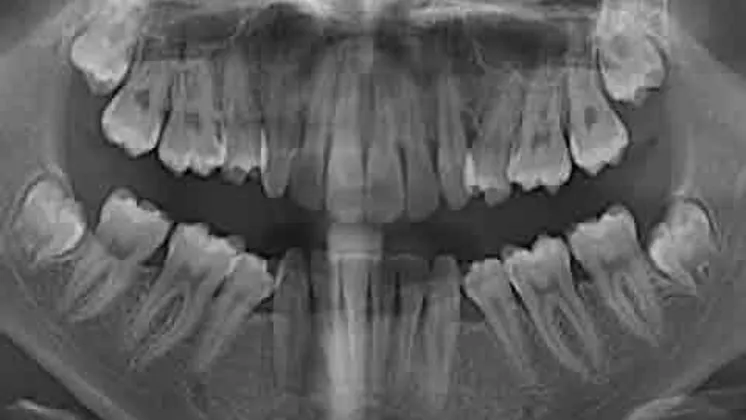

Cbct

• Beeldvorming